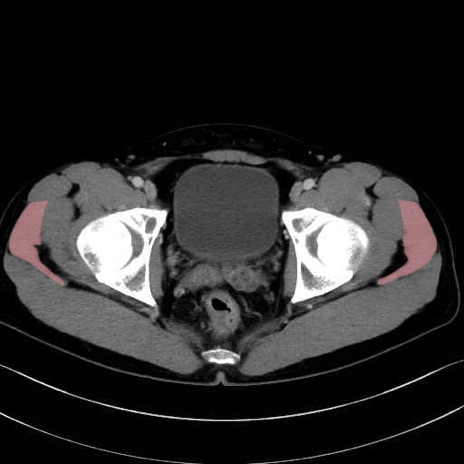

中殿筋 (Gluteus medius)